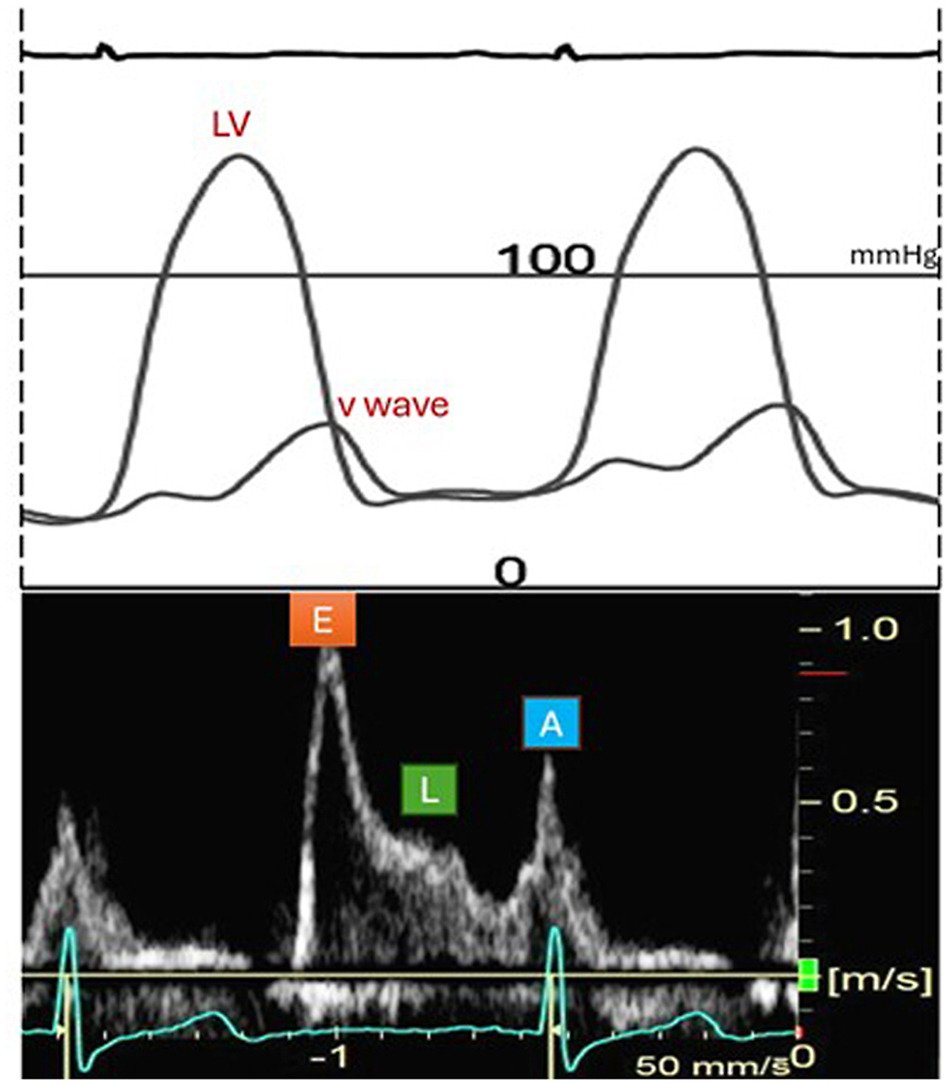

Echo DD guidelines are consensus based and require testing to determine clinical utility. In this multicenter study with gold standard dx, we show poor sensitivity and accuracy for resting and exercise echo criteria. @JACCJournals